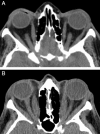

Graves' disease (GD) is a common autoimmune condition. At its core, stimulatory autoantibodies are directed at the thyroid-stimulating hormone receptor (TSHR), resulting in dysregulated thyroid gland activity and growth. Closely associated with GD is the ocular condition known as thyroid-associated ophthalmopathy (TAO). The pathogenesis of TAO remains enigmatic as do the connections between the thyroid and orbit. This review highlights the putative molecular mechanisms involved in TAO and suggests how these insights provide future directions for identifying therapeutic targets. Genetic, epigenetic, and environmental factors have been suggested as contributory to the development of GD and TAO. Thyroid-stimulating hormone receptor and insulin-like growth factor receptor (IGF-1R) are expressed at higher levels in the orbital connective tissue from individuals with TAO than in healthy tissues. Together, they form a functional complex and appear to promote signaling relevant to GD and TAO. Orbital fibroblasts display an array of cell surface receptors and generate a host of inflammatory molecules that may participate in T and B cell infiltration. Recently, a population of orbital fibroblasts has been putatively traced to bone marrow-derived progenitor cells, known as fibrocytes, as they express CD45, CD34, CXCR4, collagen I, functional TSHR, and thyroglobulin (Tg). Fibrocytes become more numerous in GD and we believe traffic to the orbit in TAO. Numerous attempts at developing complete animal models of GD have been largely unsuccessful, because they lack fidelity with the ocular manifestations seen in TAO. Better understanding of the pathogenesis of TAO and development of improved animal models should greatly accelerate the identification of medical therapy for this vexing medical problem.